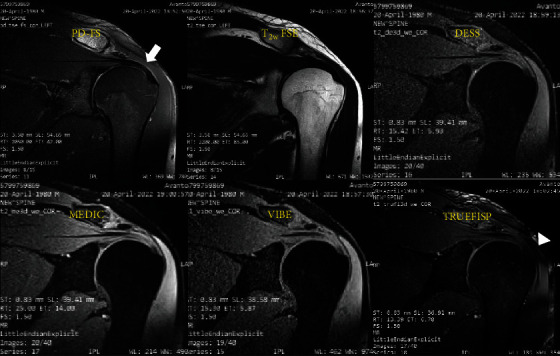

Background: Three-dimensional gradient-echo (3D-GRE) sequences provide isotropic or nearly isotropic 3D images, leading to better visualization of smaller structures, compared to two-dimensional (2D) sequences. The aim of this study was to prospectively compare 2D and 3D-GRE sequences in terms of key imaging metrics, including signal-to-noise ratio (SNR), contrast-to-noise ratio (CNR), glenohumeral joint space, image quality, artifacts, and acquisition time in shoulder joint images, using 1.5-T MRI scanner. Methods: Thirty-five normal volunteers with no history of shoulder disorders prospectively underwent a shoulder MRI examination with conventional 2D sequences, including T 1- and T 2-weighted fast spin echo (T1/T2w FSE) as well as proton density-weighted FSE with fat saturation (PD-FS) followed by 3D-GRE sequences including VIBE, TRUEFISP, DESS, and MEDIC techniques. Two independent reviewers assessed all images of the shoulder joints. Pearson correlation coefficient and intra-RR were used for reliability test. Results: Among 3D-GRE sequences, TRUEFISP showed significantly the best CNR between cartilage-bone (31.37 ± 2.57, p < 0.05) and cartilage-muscle (13.51 ± 1.14, p < 0.05). TRUEFISP also showed the highest SNR for cartilage (41.65 ± 2.19, p < 0.01) and muscle (26.71 ± 0.79, p < 0.05). Furthermore, 3D-GRE sequences showed significantly higher image quality, compared to 2D sequences (p < 0.001). Moreover, the acquisition time of the 3D-GRE sequences was considerably shorter than the total acquisition time of PD-FS sequences in three orientations (p < 0.01). Conclusions: 3D-GRE sequences provide superior image quality and efficiency for evaluating articular joints, particularly in shoulder imaging. The TRUEFISP technique offers the best contrast and signal quality, making it a valuable tool in clinical practice.